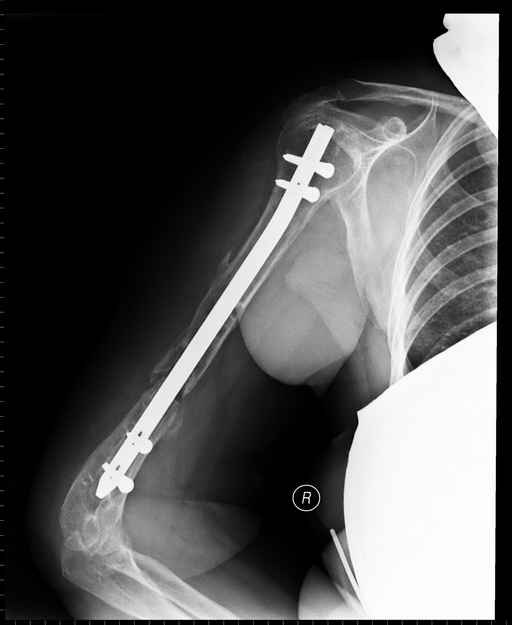

Больная 48 лет, медсестра-массажист, перелом плеча 7 лет назад, оперирована 4-кратно и безуспешно

Больная 48 лет, медсестра. Травма получена 7 лет назад, оперирована первично в Турции - остеосинтез пластиной - несращение - реостеосинтез стержнем там же через год (обычным, с выстоянеием его в полость плеча) - несращение - поступила к нам впервые в марте 2008 года - удаление стержня, реостеосинтез пластиной и костная пластика, в течение 2 лет лизис кости вокруг винтов, смещение фиксатора, в марте 2010 - удаление пластины, реостеосинтез интрамедуллярным стержнем с блокированием (рассверливание + костная пластика). В динамике - вновь лизис в области перелома, нестабильность дистальных блокирующих винтов.

Да, принципиально что-то такое тут подошло бы. Но тут дефект, и надо точно подсчитать, не длинноват ли стержень, а то, может, после плотного контакта он вылезет в локтевую ямку.

Клинически фиксация пока действительно стабильна, но на рентгенограммах резорбция кости в области дистальных блокирующих винтов и миграция одного из них.